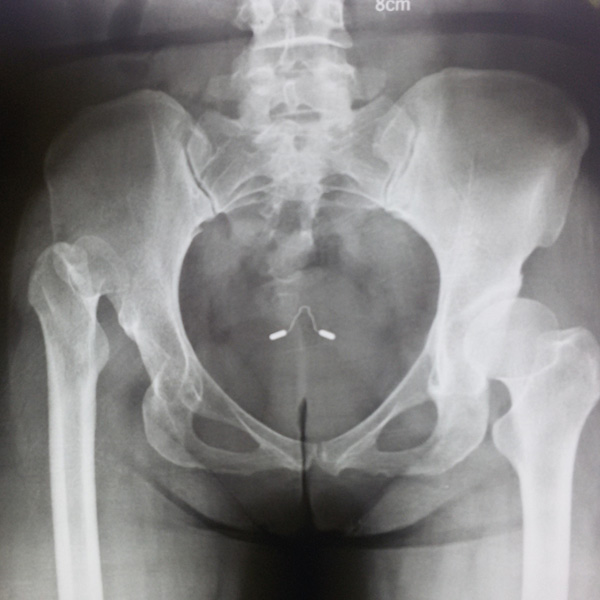

先天性髖關節脫位

患者王某某,女,41歲,從會走路以來就發現一條腿長,一條腿短,也就是人們俗稱的“跛子”,之前雖然兩條腿長短不一,但起碼還可以走路,維......